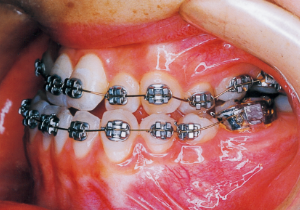

2 After Phase 2 Treatment 5-9-’92

Aware that treatment would be challenging, we proceeded with the first phase of treatment based on the current functional status and anticipated developmental implications (7). During the mixed dentition phase, the body responds readily to treatment, allowing for relatively rapid tooth movement and changes in jaw position (8,9). Subsequently, once freed from mechanical stimulation, growth continues according to inherent predispositions, often appearing to disregard occlusal functional efficiency (10,11). These changes are clearly observable on cephalometric radiographs (12). After confirming the extent and direction of growth, we decided to incorporate surgical intervention into the treatment plan and wait until the age when growth begin to decline.

13 5-21-’90 At Phase 2 Treatment

14 6-21-’90 Beginning of second phase

15 3-23-’91 Before surgery

16 5-9-’92 After Phase 2 Treatment